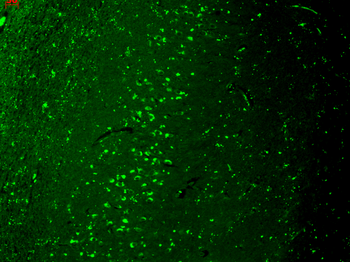

Immunofluorescence analysis of HepG2 cells using TRPV1 antibody